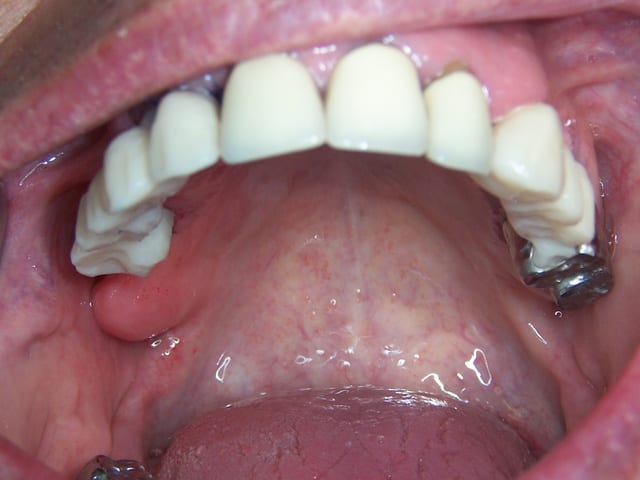

2010 bridge provisoire sur ANKYLOS, extaction, mise en charge immédiate bridge provisoire à armature métal sans scellement en 1 seul temps chiurgical.

Chirurgie à PAMIERS, préparation prothétique et dispositif de forage à MONTASTRUC LA CONSEILLERE, dans notre belle campagne de France.